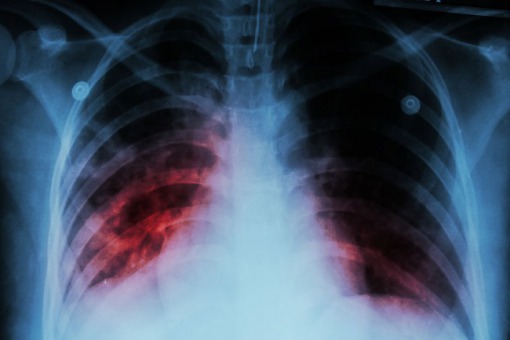

Co Koronawirus Robi Z Plucami Wstrzasajace Zdjecia Wloskich Lekarzy